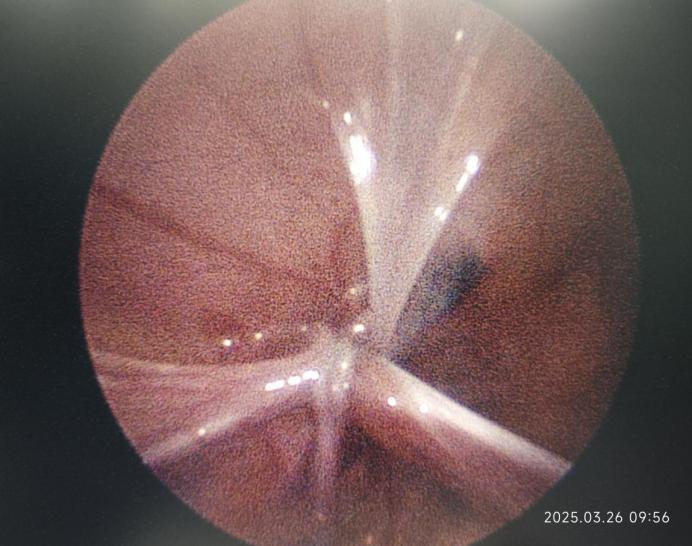

手术过程中的情况

2mm腹腔镜下单孔结扎内环口完毕 2mm腹腔镜术后切口情况